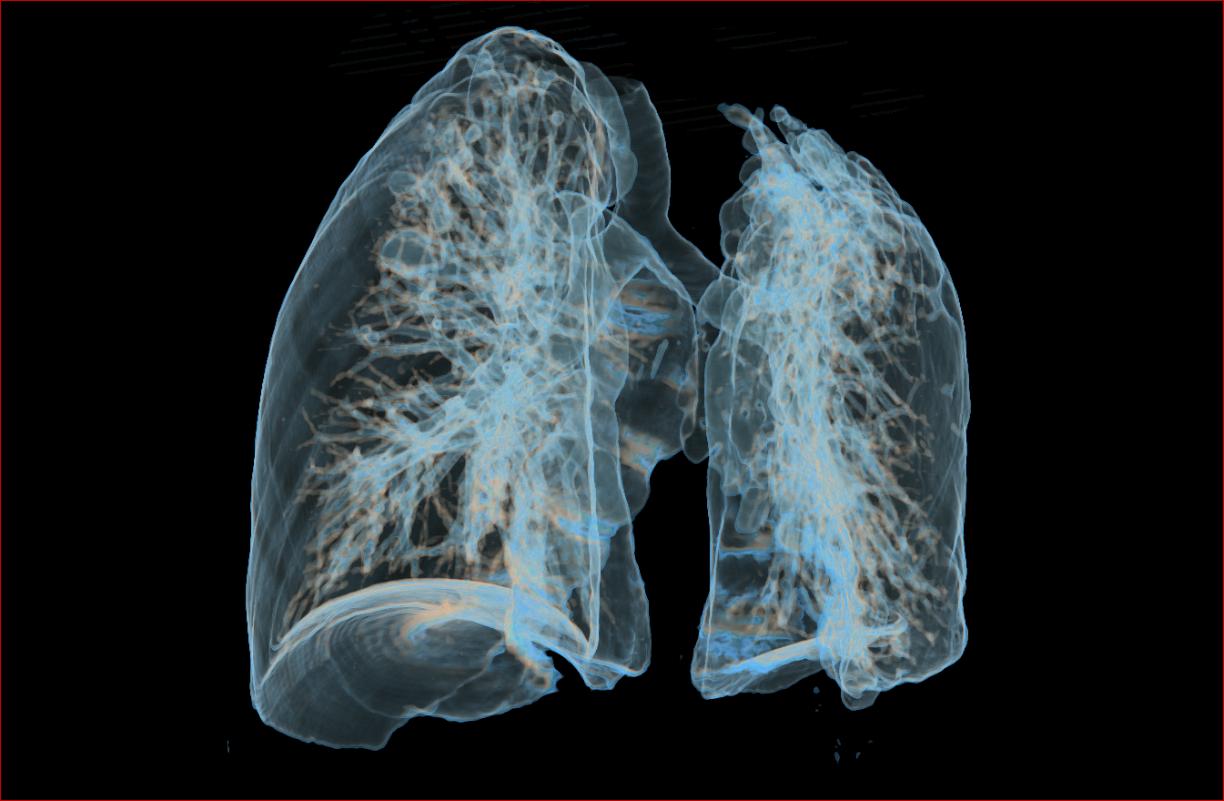

肺结核是由结核分枝杆菌引起的传染病,主要通过空气、飞沫经呼吸道传染。

肺结核多表现为慢性病程,症状有时候很不典型。如果在患者的痰或病理策划中没有找到结核分枝杆菌,诊断有时候比较困难。

肺结核最好的确诊方式,是病原学诊断。

病原学诊断,就是在病人的痰液、分泌物或者病理策划里面,直接涂片找到结核杆菌,或者培养出结核杆菌,或检测出结核杆菌的核酸(DNA)。